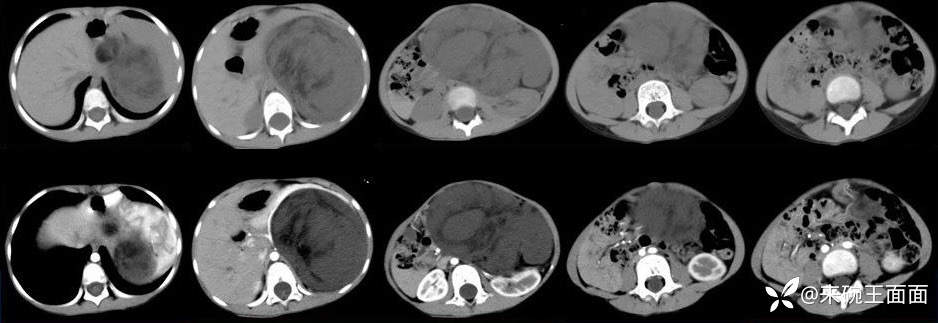

[现病史]1月余前无明显诱因发现左上腹肿物,无发热,无呕吐,无腹痛、腹泻、排便困难及其他不适,无尿频尿急,至当地医院CT示左上腹巨大占位性病变。【体格检查]腹膨隆,未及胃肠型及蠕动波,未及腹壁静脉曲张,腹软,左上腹可及大小约10*10cm肿物,质中,位置固定,无压痛、反跳痛,肝脾肋下未及,移动性浊音阴性,肠鸣音4-5次/分。

左上腹巨大软组织肿块影,密度混杂,边界清楚,其内可见脂肪密度,增强扫描未见强化。